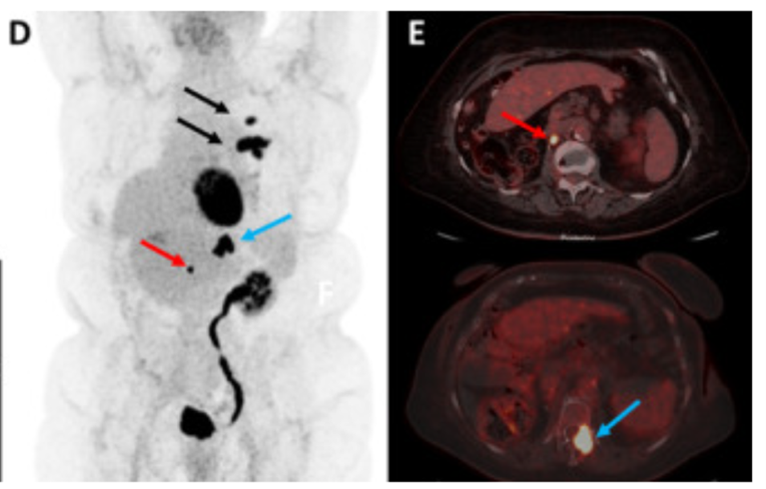

- Role of PET Imaging: 18F-Fluorodeoxyglucose (FDG PET) is a radiotracer with a glucose component. Cancer cells are metabolically active relying on glycolysis, and therefore may have preferential signal or ‘avidity’.45 However, there can be false signal because, like IV contrast, FDG PET tracer can also opacify and mask ‘avid signal’ when its excreted through upper tract. Outside of the urinary tract, PET/CT can help detect metastases and clinically relevant nodes.46

Figure 7: FDG PET avid signal corresponding to retroperitoneal lymph nodes (red arrow), lung metastasis (black arrow), and bone metastasis to spine (blue arrow) following nephroureterectomy for UTUC Source: https://www.sciencedirect.com/science/article/pii/S0001299821001057#fig0006

Imaging can assist in the staging of UTUC, evaluating both local and distant ie metastatic disease. Given the challenges of adequate staging and grading with ureteroscopic biopsies, imaging can add additional useful information. On CT imaging, heterogeneous texture on contrast and noncontrast imaging can suggest higher risk disease. While it is intuitive to assume that hydronephrosis is associated with more aggressive disease, there has been some variability in the literature regarding this finding. (GL) CT is also useful to evaluate for enlarged regional and distant lymph nodes, which could suggest metastatic disease. Finally, CT is also utilized to evaluate for lung metastases or other sites of metastatic disease (liver in particular). MRI is helpful in patients who cannot receive intravenous contrast for CT. Positron Emission Tomography (PET) imaging is utilized by some in the staging of UTUC, though its role in management remains unclear as more data evolves. One series found the sensitivity to be 82% and the specificity 84% in regard to lymph node metastases in patients undergoing surgery.50